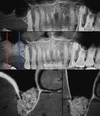

الصور